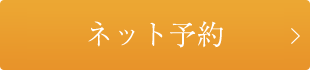

47番を破折にて抜歯後、2カ月したレントゲンです。

頬側の骨がかなり落ちくぼんでおり、今後もかなりの量の骨の吸収が予想されますので、GBRを併用した移植を計画しました。